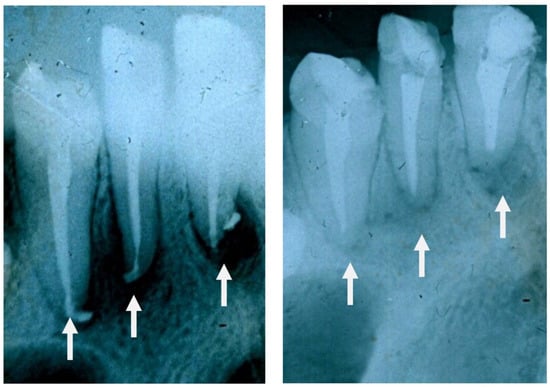

The same 1d glass particulate was clinically tested over 8 months to treat jawbone defects in human patients mainly after a cystectomy operation. The test was conducted in 45 volunteers (21 males and 24 females) aged between 19 and 60. Patients were examined before and after surgery at 2 weeks, 2 months and 6 months. In this study, glass particles were inserted where there was a defect in the alveolar bone in order to avoid the progressive loss of bone over time (resorption) and assure the stability of the patient’s teeth. These early clinical trials showed that the glass formed a cohesive mass with the patient’s blood, thus demonstrating a homeostatic effect. Figure 11 shows that new, regenerated bone was formed after 2 months where there was the empty space of a jawbone defect before surgery. Similar results were found in all patients and, thus, these early clinical trials support the suitability of 1d glass for the conventional treatment of bone defects (highly biocompatible and bioactive filler). Figure 12 shows two other radiographs of the patient showing that after a cystectomy operation, the lesions were filled up with newly formed cancellous bone. However, in order to gain regulatory approval and consider this bioactive glass for routine surgery, it will be necessary to increase the number of patients during a further phase of clinical trials.

Figure 11. Radiographic images of jawbone defects before ((left) side) and after surgical intervention (2 months of follow-up) with implantation of 1d glass particulates ((right) side). Reproduced from [26] with permission.

Figure 12. High-magnification radiographs of the patient before ((left) side) and after 2 months from operation ((right) side) showing that the lesions were filled up with trabeculae of new bone.